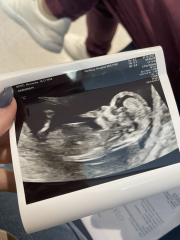

xalexandra · 07/10/2022 10:25

Just had my 12 week scan and all fine and healthy 🥰🥰 I mentioned about the fluid again after yesterdays hospital trip and she said it seems fine 🥰

@xalexandra yaaaay! So happy for you ! Gorgeous scan, looks like a boy to me 🤣 x

@Sprinklerainbows omg someone else said boy! Maybe you're on to something!!

@xalexandra It’s the nub looks high up but I’m no expert by any means 🤣 I have a boy and it’s the best!